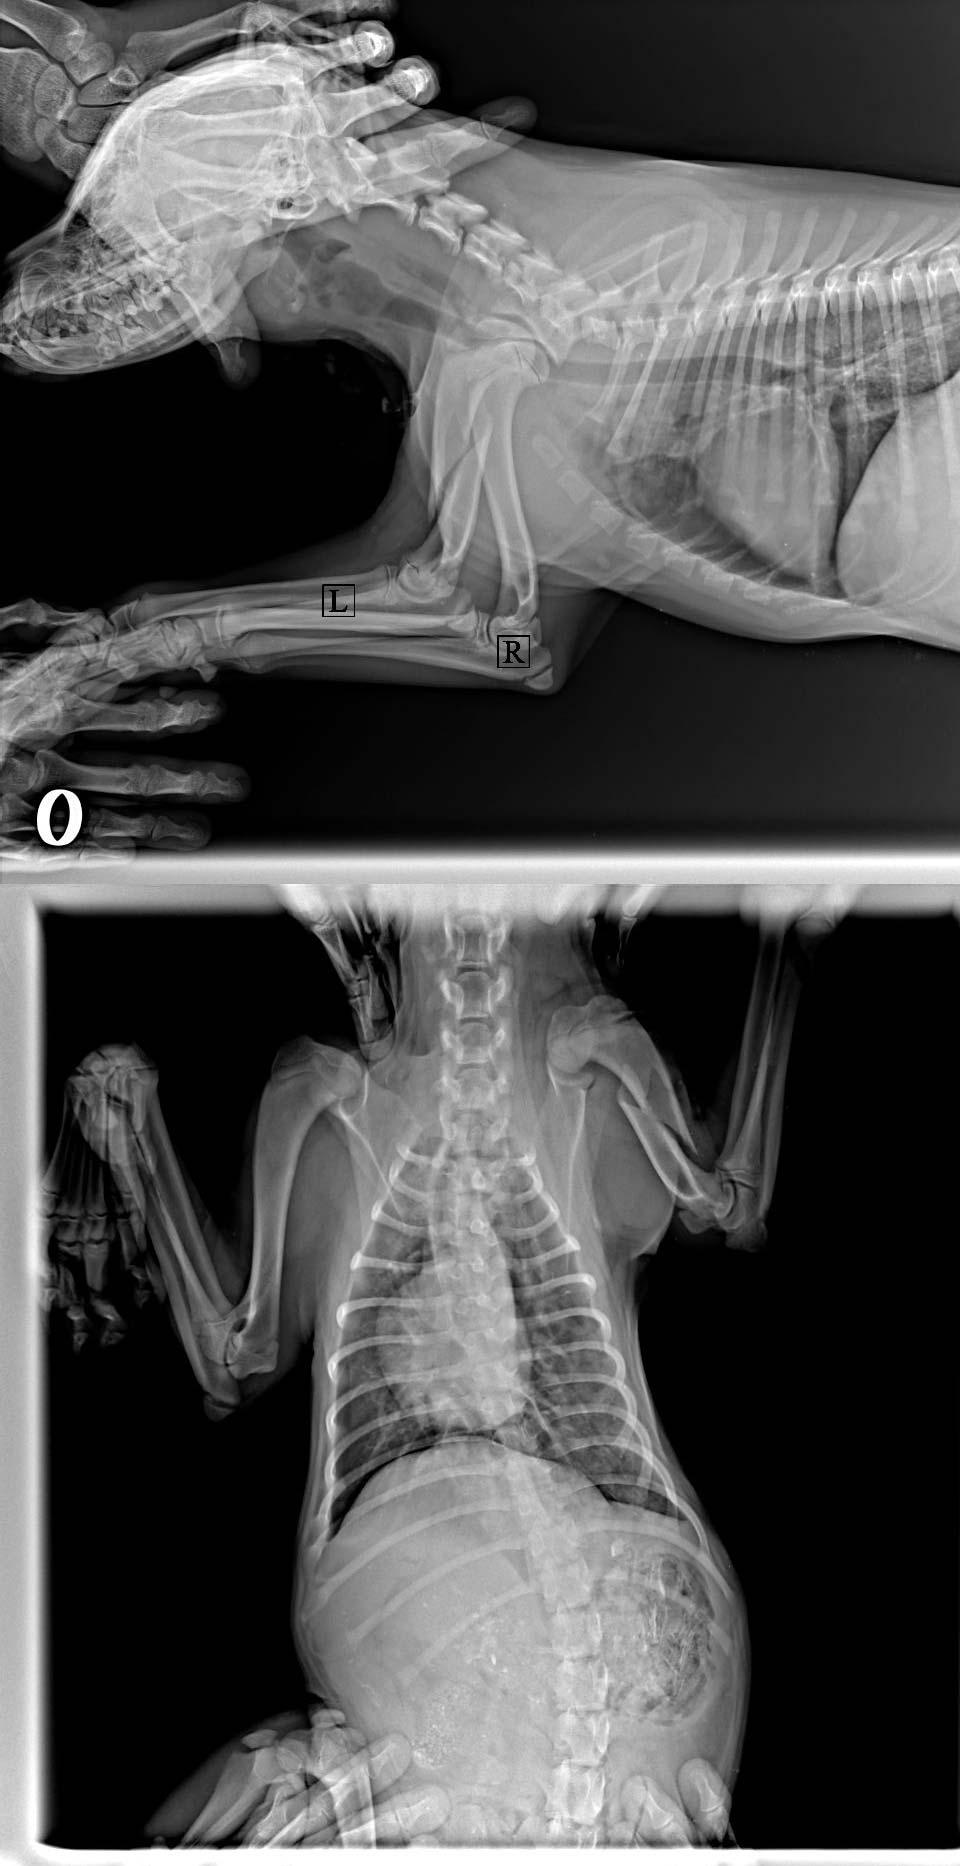

В ветеринарной клинике собаку осмотрели, сделали рентген и врач сообщил сразу о трех серьезных переломах.

Из заключения: "Перелом голени левой тазовой конечности, бедренной кости левой тазовой конечности, плеча левой грудной конечности".